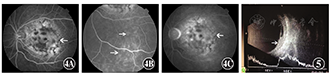

患者,女,42岁。2015年9月因左眼视物不清1个月于沧州市中心医院就诊,左侧颜面部可见血管瘤(图1)。眼科检查:视力右眼1.0,左眼0.1,右眼前后节未见异常,左眼鼻侧球结膜血管迂曲扩张,颞侧球结膜表面可见肿物,突出于眼表(图2),角膜透明,晶状体无明显混浊,玻璃体检查未见明显异常,眼底检查可见黄斑区类圆形橘黄色隆起,大小约为4个视盘直径(papillary diameter,PD)(图3)。颅脑CT未见异常;荧光素眼底血管造影(fundus fluorescein angiography,FFA)显示左眼静脉期黄斑区脉络膜高低荧光相间,病灶下方可见点片状高荧光,晚期黄斑区及其下方荧光素稍渗漏(图4);眼部B型超声检查显示左眼球壁局限性卵圆形隆起,突向玻璃体腔,表面光滑,内回声均匀,中等强度,其边缘可探及带状回声(图5);眼部彩色超声检查显示左眼颞侧靠近球壁可见一囊性结构,形态规则,其内呈现液性区,内透声可,彩色多普勒血流显像(color doppler flow imaging,CDFI)示其内未见血流信号,视盘颞侧可见一偏强回声,内部回声均匀,其内可见丰富血流信号,该处视网膜稍隆起,并可见一带状回声与之相连(图6);OCT显示黄斑区脉络膜及其上结构高度隆起,相应处视网膜神经上皮层浆液性脱离,层间水肿,视网膜色素上皮(retinal pigment epithelium,RPE)/脉络膜毛细血管光带不完整(图7)。诊断:斯特奇-韦伯综合征(Sturge-Weber syndrome,SWS)。